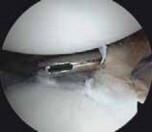

Anchor Placement and Capsulolabral Plication

With the glenoid prepared and the tissue mobilized, fixation begins at the most inferior aspect of the lesion, typically at the 5:30 or 6 o'clock position. Modern fixation relies on either biocomposite or all-suture anchors, typically 1.5 mm to 2.9 mm in diameter. The drill guide is introduced through the anteroinferior portal, and the anchor is deployed on the articular margin (1-2 mm onto the articular cartilage face) to recreate the anatomical labral bumper. The trajectory of the drill is paramount; it must be directed slightly medially to avoid penetrating the articular surface of the glenoid vault.